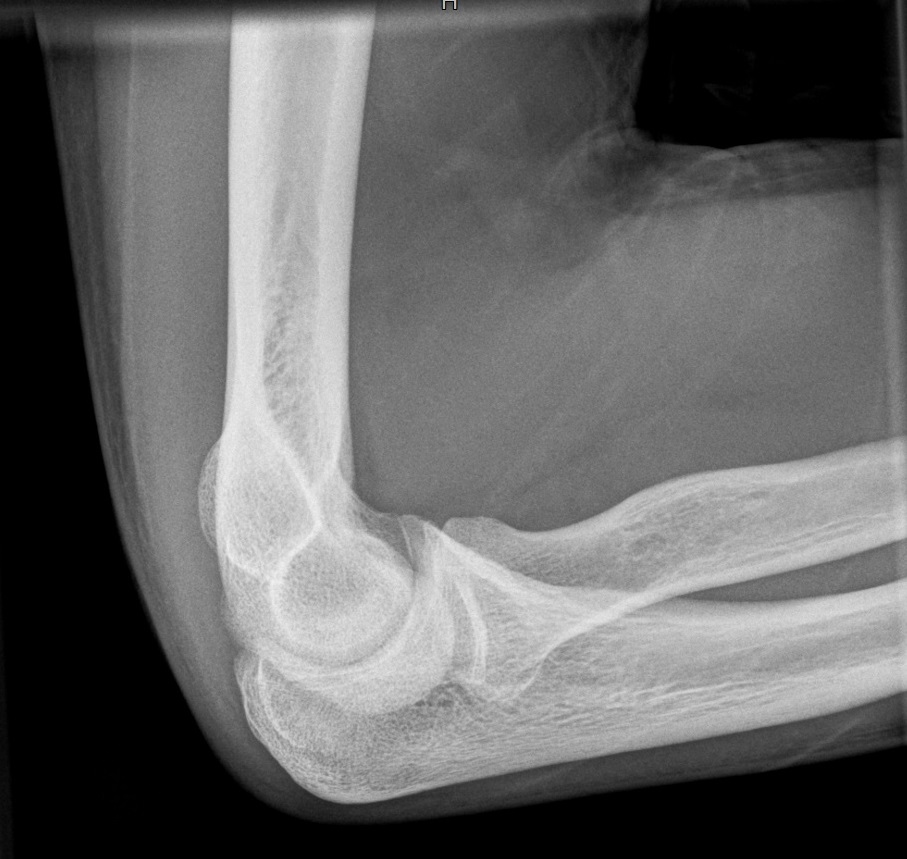

Ellenbogen

Ellenbogen a.p.

Fehler

Der Gelenkspalt zwischen Humerus und Radiusköpfchen ist nicht frei; die Gelenkfläche des Radiusköpfchen ist stark oval gezeichnet und verdeckt die Gelenkfläche des Humerus. Der Patient kippte den Vorderarm mit der Hand hoch statt sie flach aufzulegen.

Abhilfe

Es müssen Vorder- und Oberarm streng gestreckt gehalten werden.